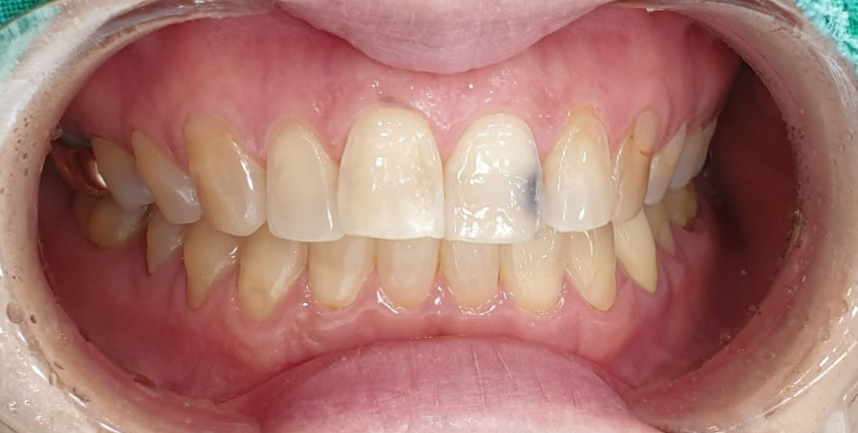

치료 전 사진 / 2025. 06. 02

이때 생기는 까만 변색이 단순한 착색인지, 심각한 충치인지 구분이 필요합니다. 겉으로는 멀쩡해 보여도, 내부에서 충치가 진행되었을 수 있어요.

앞니는 기능뿐 아니라 심미적으로도 매우 중요한 위치입니다. 검은 점이나 변색이 보인다면, 단순히 미용 문제가 아니라 신경 손상의 신호일 수 있습니다.